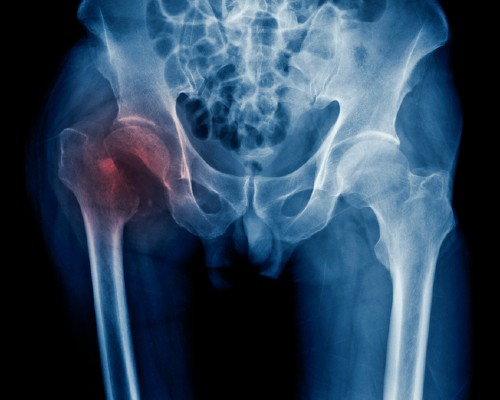

New Guidance on Hip Fracture Services Will Improve Recovery for Thousands of Patients

Every year more than 70,000 older adults are admitted to a UK hospital after a hip fracture, which can lead to decreased quality of life, increased mortality and emergency hospital readmission after discharge.